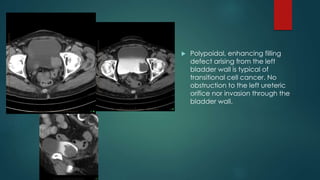

 Polypoidal, enhancing filling

defect arising from the left

bladder wall is typical of

transitional cell cancer. No

obstruction to the left ureteric

orifice nor invasion through the

bladder wall.